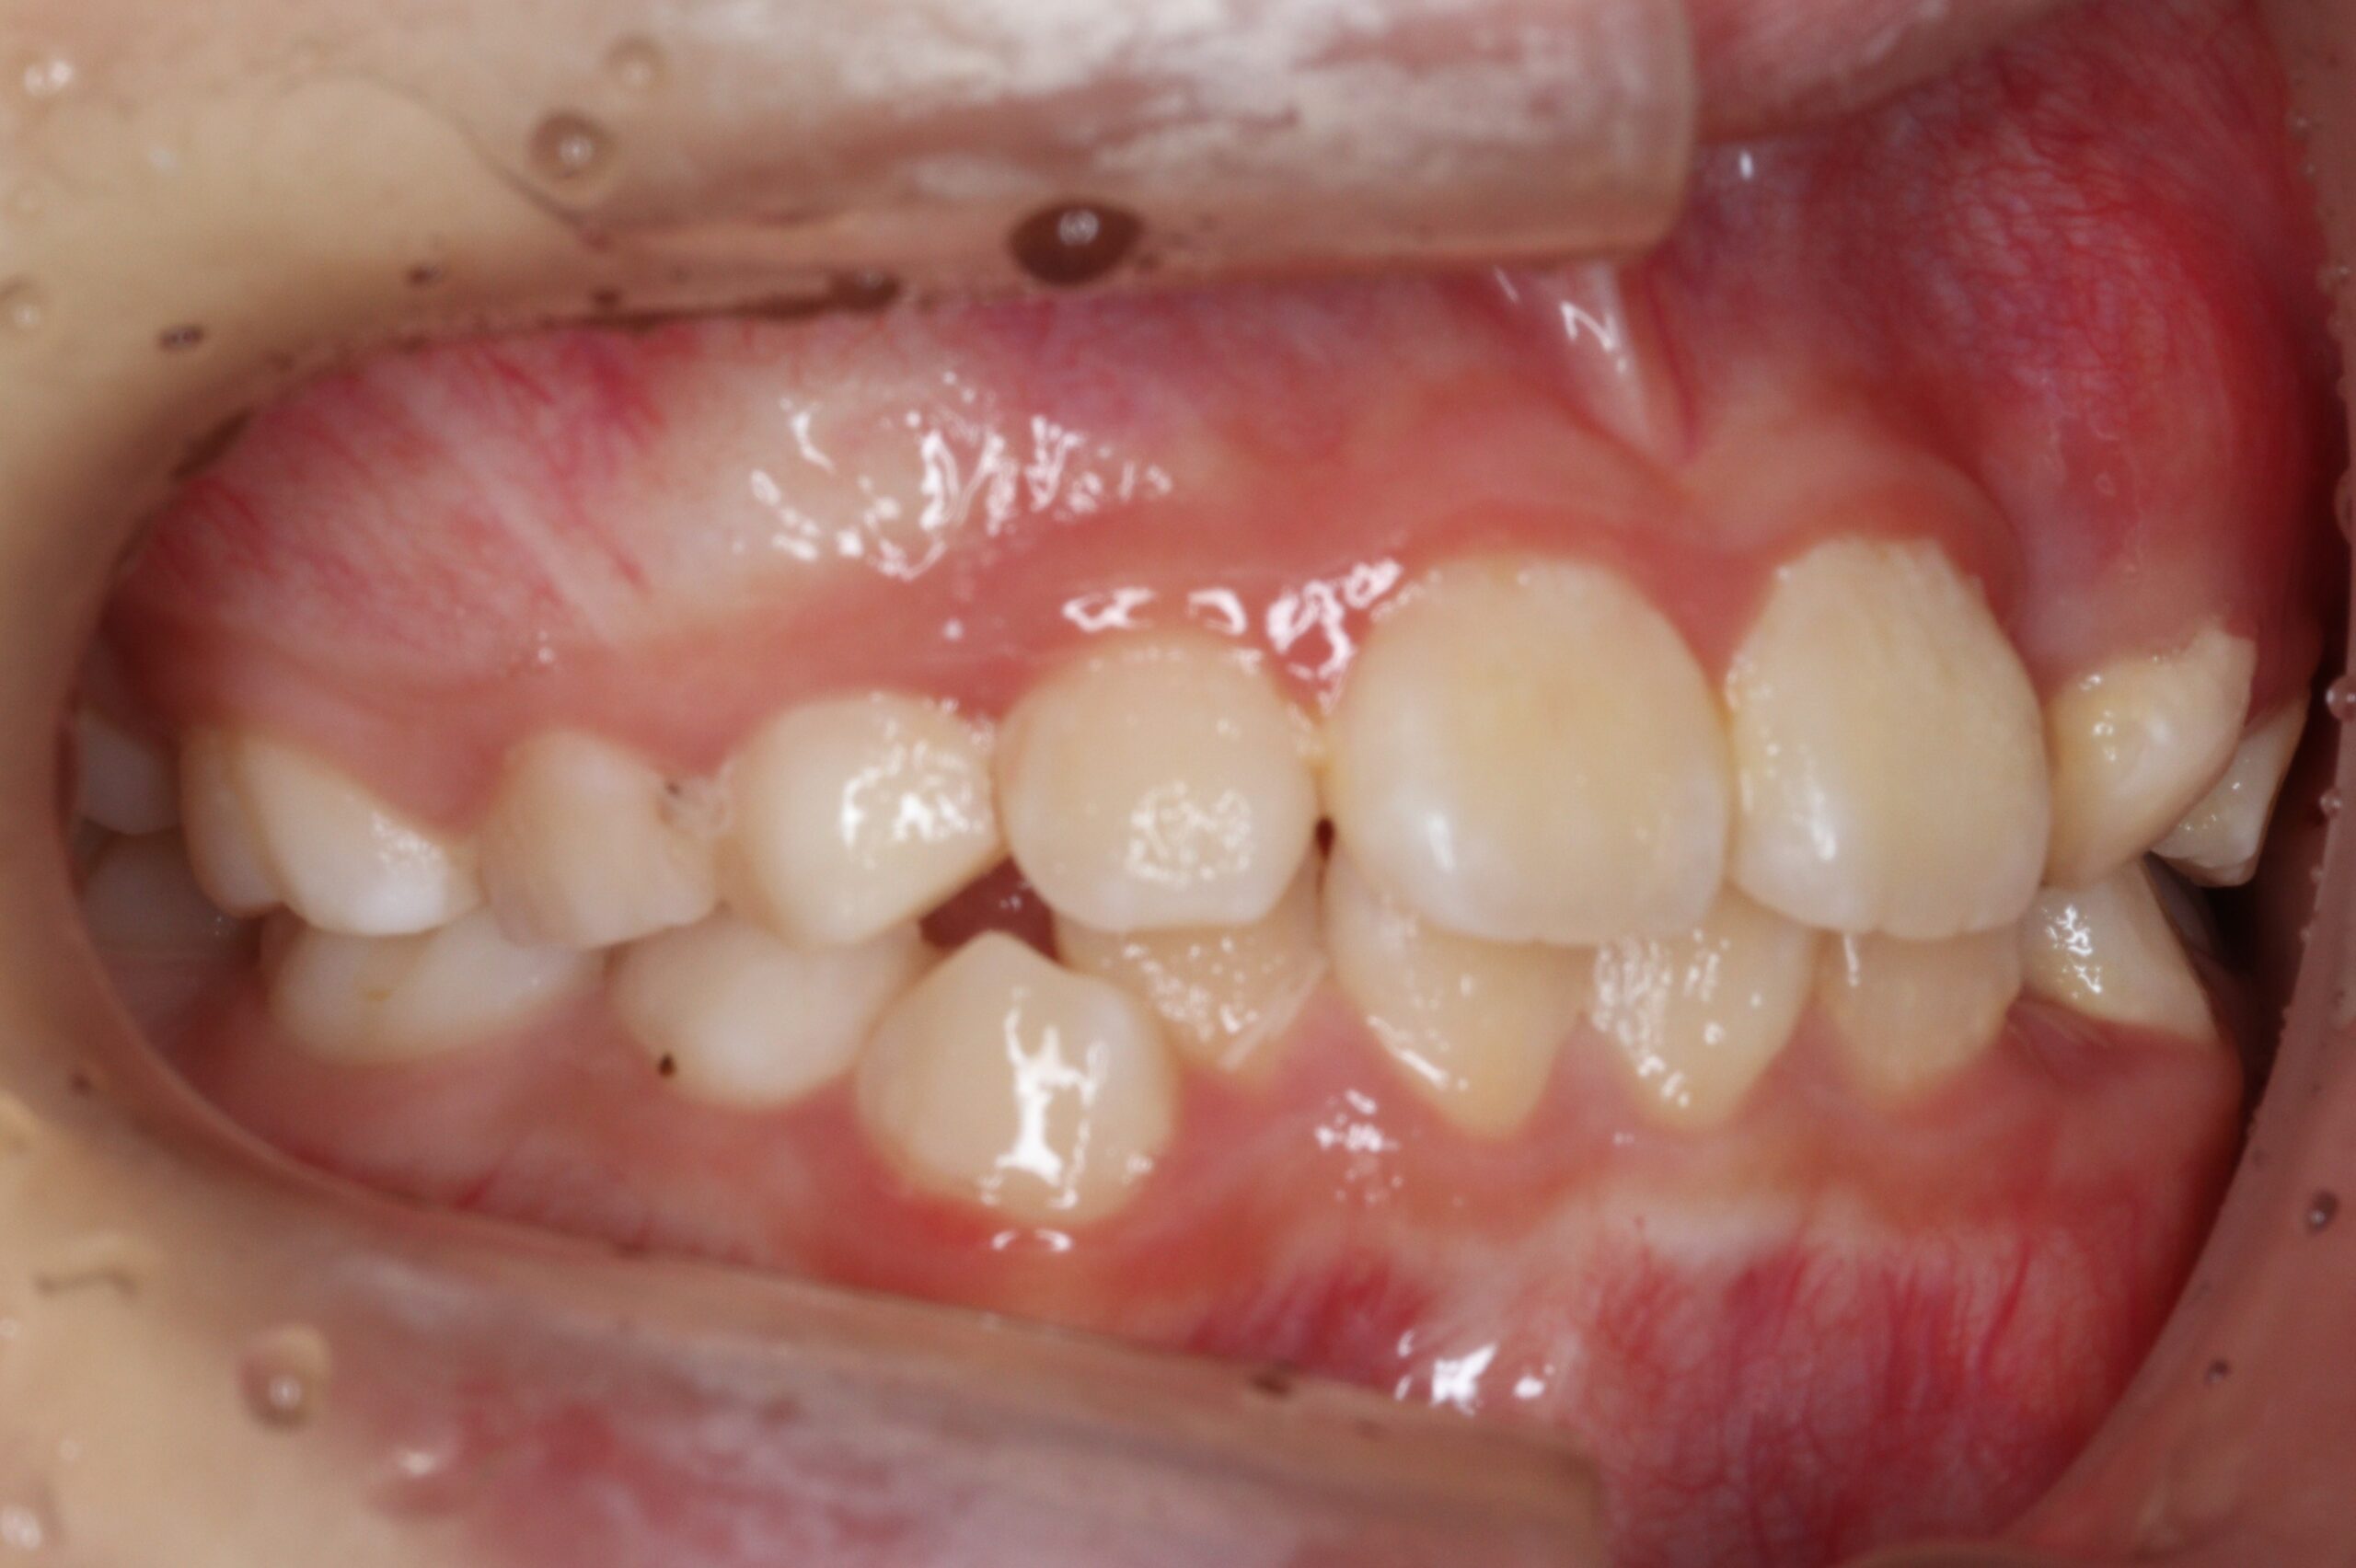

矯正術前:右側

今回ご紹介する患者様は、全体的な歯並びのがたつきを気にされており、矯正検査後叢生Ⅰ級と診断いたしました。

| 主訴 | 全体的な歯並びのがたつきが気になる |

| 治療内容 | 患者様は全体的な歯並びのがたつきを気にされており、矯正検査後叢生Ⅰ級と診断いたしました。 |